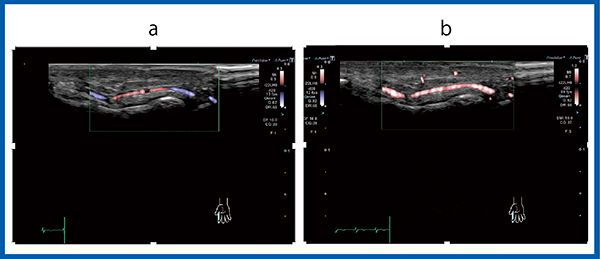

図2は,Aplio i-seriesを用いたレイノー現象の評価である。レイノー現象では,指先の血流の減少や,途絶,側副血行路の発達,cork screw signが描出される。cork screw signはバージャー病で高頻度に観察されるが,特異的な所見ではなく,慢性炎症による所見である。Aplio i-seriesで観察すると,SMIを用いることで微細な側副血行路を描出することが可能である(図2)。また,7MHzマトリックスリニアプローブPLI-705BXによる足背動脈でのカラードプラ,ADF,SMIの比較では,SMIの方が明瞭に血流が描出されている(図3)。さらに,プローブによっても見え方が大きく変わる。図4 aはPLI-705BXで,図4 bはPLI-2004BXであるが,PLI-2004BXの方が血流がなめらかで,SMIの描出能も向上している。

図4 プローブの描出能の違い

a:PLI-705BX b:PLI-2004BX